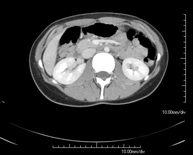

- Abdominal and pelvic CT

Diagnostic test that consists of obtaining high-definition anatomical images (bone structures, vascular structures, liver, pancreas, gallbladder, kidneys, adrenal glands, spleen, small and large intestine, bladder, uterus and ovaries, prostate and seminal vesicles, ureters, etc.) using CT (computed tomography) equipment. Most studies require the use of iodinated contrast.